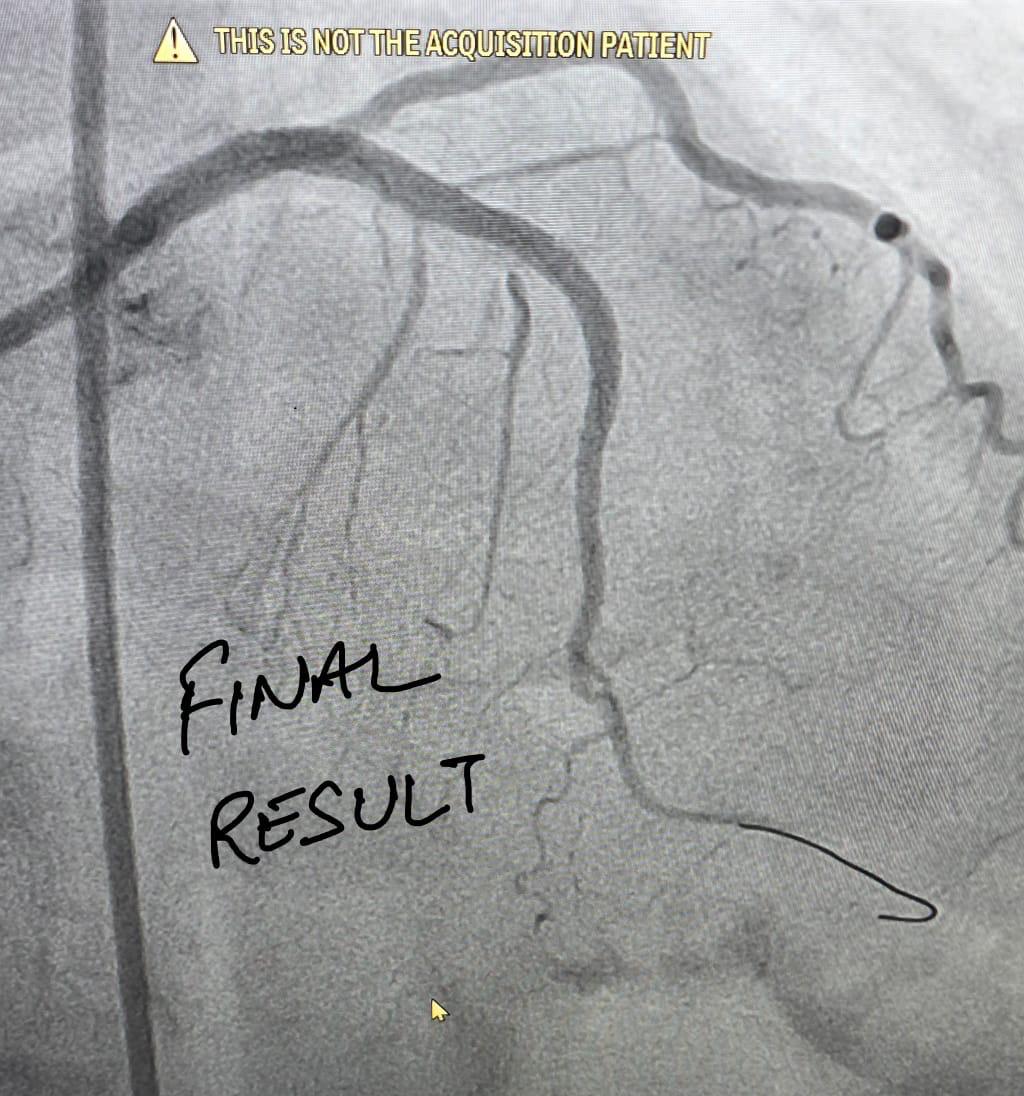

Intravascular Lithotripsy (IVL)

Intravascular Lithotripsy (IVL) is an advanced medical technology used in cardiovascular treatments. It is designed to break down calcium deposits inside blood vessels. By doing so, it helps improve blood flow and supports better outcomes for patients with heart disease.

IVL is a minimally invasive procedure that uses sonic pressure waves. These waves target hardened calcium within the arteries. The device works like traditional kidney stone lithotripsy but inside blood vessels. It prepares the artery for stent placement and reduces complications.

The procedure involves inserting a specialized catheter with a balloon into the artery. Once in place, the balloon emits controlled sonic pulses. These pulses fracture the calcium deposits. After that, the artery can expand properly, making stent placement easier and safer.